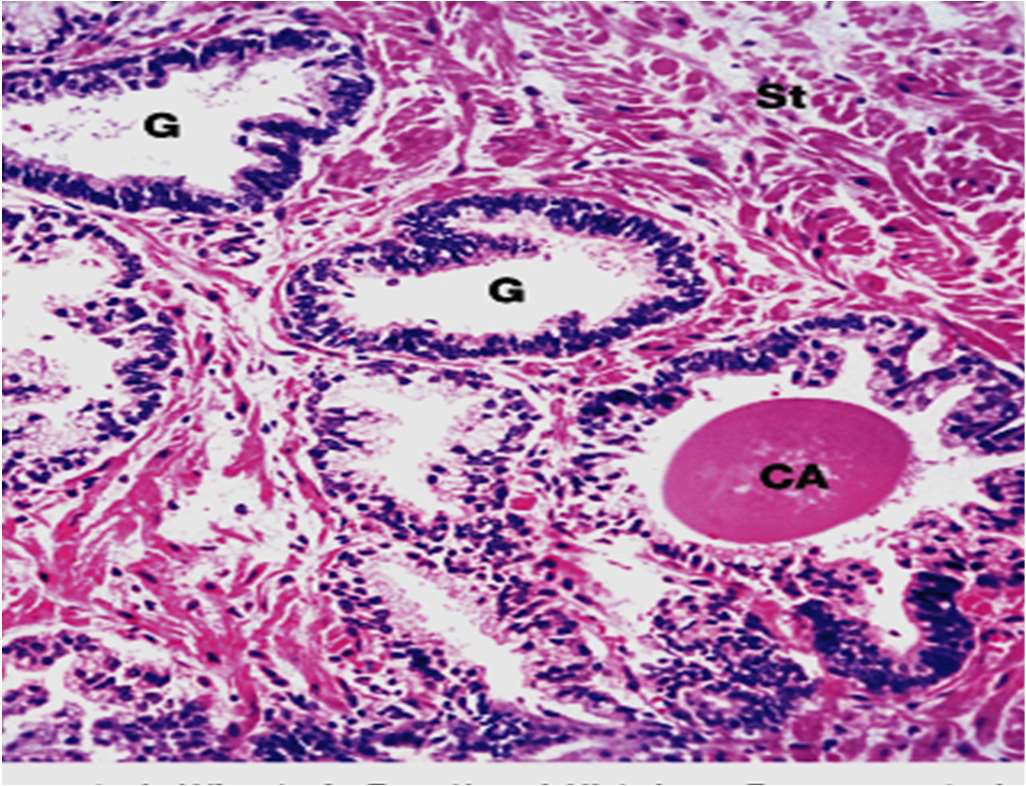

Testes

Seminiferous tubules

Sertoli cell (St)

Interstitium

Leydig cell

Efferent Ductule

Epididymis